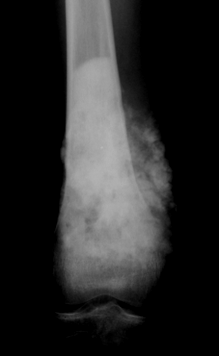

骨肉瘤是一种常见的恶性骨肿瘤,主要发生在青少年,尤其是膝关节附近的长骨端(如股骨、胫骨等)。骨肉瘤的发病率约为每百万3-4例。尤文肉瘤则是一种恶性的小圆细胞肿瘤,通常发生在骨骼和软组织中,也常见于儿童和青少年。它是继骨肉瘤之后,第二常见的原发性恶性骨肿瘤,发病率大约为每百万1.5例,男孩的发病率稍高于女孩。最常见的发病部位包括骨盆、股骨、胫骨和肋骨等骨骼部位,也可发生在软组织中,如胸壁、臀部和脊柱旁等。(图1)

图1 骨肉瘤和尤文肉瘤的好发部位 (Arndt CA, Crist WM. Common musculoskeletal tumors of childhood and adolescence. N Engl J Med. 1999;341(5):342-52.)